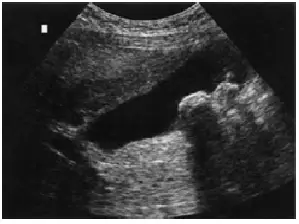

下列腹部超音波影像診斷最可能為:

A膽囊息肉( gallbladder polyp )

B急性膽囊炎( acute cholecystitis )

C膽囊肌腺瘤( gallbladder adenomyomatosis )

D膽囊結石( gallbladder stone )

本題超音波圖像呈現膽囊(gallbladder)影像,可觀察到以下關鍵特徵:

- 膽囊腔:呈無回音(anechoic)液體充填,輪廓清晰

- 高回音病灶:膽囊腔的依重力方向(dependent portion,通常為下方)可見一個或多個強高回音(hyperechoic)病灶,亮度明顯高於周圍組織

- 後方聲影(posterior acoustic shadow):在高回音病灶的遠端(posterior),可見明顯的無回音聲影帶(acoustic shadow),呈楔形延伸至影像下方,此為結石完全阻斷超音波傳導的典型表現

- 移動性:結石受重力影響會隨病患體位改變而移動(此在靜態圖像中無法直接顯示,但為重要的診斷確認方式)

- 膽囊壁:無明顯增厚或壁層分層現象

以上影像特徵——高回音病灶 + 後方聲影